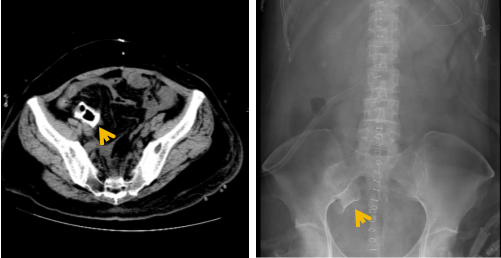

得益于邓大姐的全身心信任与配合,在医护团队的通力合作下,邓大姐术后恢复迅速,顺利进食,转流管引流通畅。术后复查显示支架位置良好,肝肾功能等指标稳定,术后第二周复查CT及腹部平片可见完整支架影。

术后盆腔CT及腹部平片可见完整小肠支架影子(箭头)

邓大姐于术后第三周如期开始了首次静脉化疗。术后第四周,影像学证实支架已完全降解,转流管成功拔除。